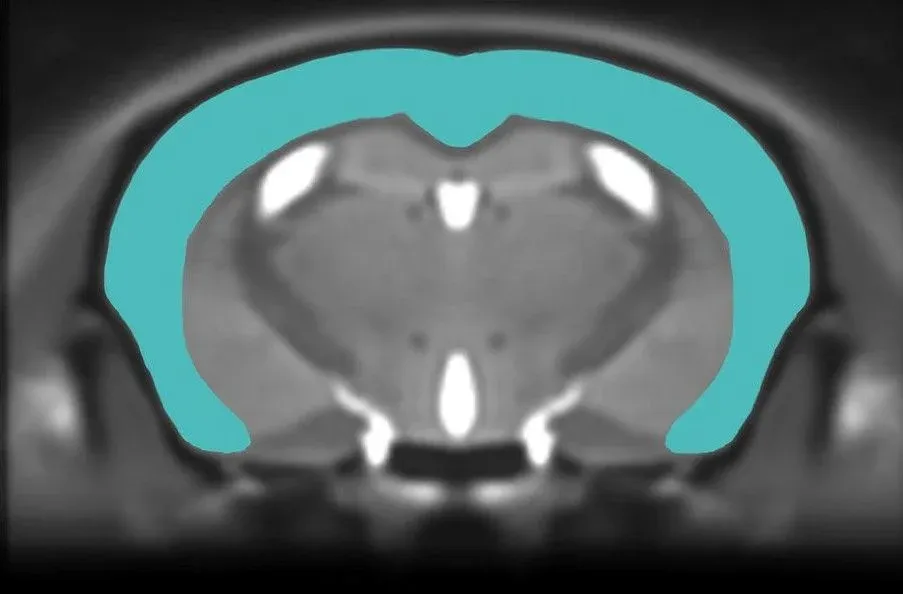

Anatomical MRI of mouse brain showing segmented cerebral cortex for measurement of cortical thickness.

Regional Brain Atrophy

Multi-modality imaging biomarkers are widely used in clinical trials of Alzheimer's disease and tauopathies. MRI-derived regional volume and cortical thickness measures are highly sensitive to brain atrophy and allow for monitoring disease progression over time in Alzheimer's disease. Using non-invasive, in vivo whole brain MRI acquisition combined with advanced, fully-automated image processing & analysis, we have shown highly significant regional brain atrophy, specifically related to tau pathology, thereby serving as a robust in-life measure of neurodegeneration and a translational biomarker.